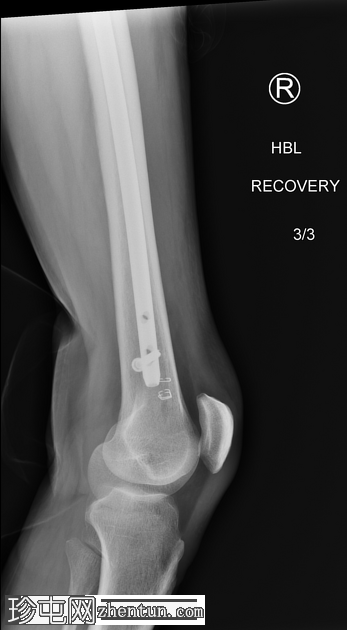

X光片

4.jpeg

正面

右侧髓内钉近端骨折(位于拉力螺钉孔位)。

空心髋螺钉组件完好。

股骨转子间骨折延伸至股骨近端转移灶,小转子粉碎。

以下为既往(及随访)影像学检查结果,供参考,展示术前股骨近端溶骨性病变、髓内钉骨折前的表现以及髓内钉骨折后的治疗情况。